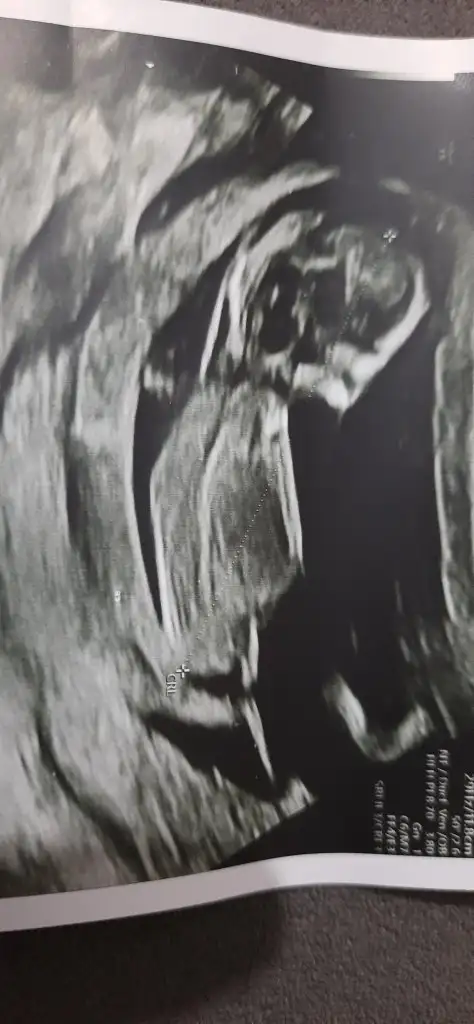

Ama bak canım benim bir tane daha var bunda karnı daha çıkık seninkine göre yine de düşük mü bilmiyorum da

Eklentiler

• 20221011_202732.webp

22,9 KB · Görüntüleme: 66